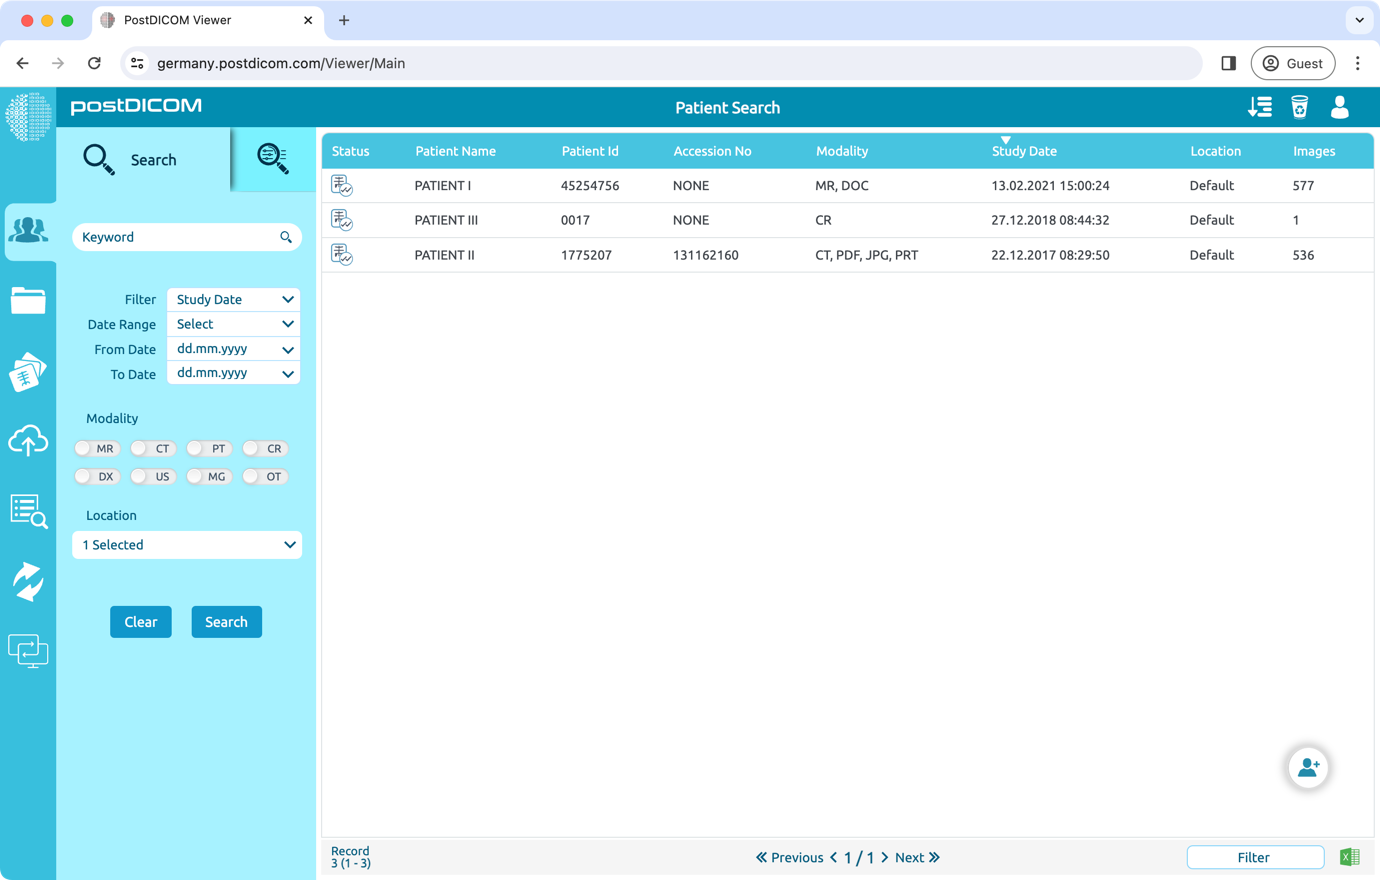

To download images with CD Viewer, open the patient study that you want to download.